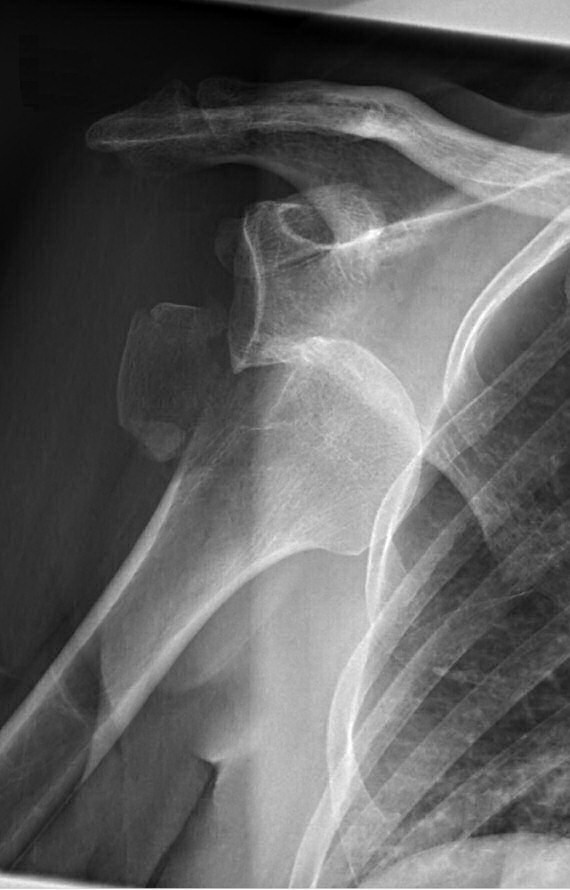

Axelluxation med avlöst tuberkulum majus innan och efter reponering i narkos. Efter reponering förbättrat läge men även misstänkt bony bankart-skada med litet fragment inferiort om glenoiden.